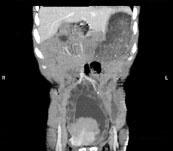

问题 男,33岁,反复尿频,尿急,尿痛3年余,排尿困难4个月,尿常规:蛋白(+),红细胞01/HP,白细胞(++),CT扫描图,下列诊断哪项说法正确 ( )

选项 A、双侧肾积水,双侧输尿管扩张 B、膀胱多发性假性憩室 C、膀胱慢性炎性肉芽肿 D、膀胱癌 E、膀胱结石

答案 ABCE